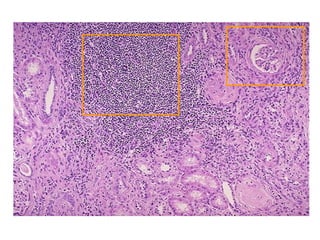

ACUTE or CHRONIC PYELONEPHRITIS?

GROSS

• Shrunken , scarred kidneys.

• If both kidneys are involved - involvement is asymmetrical

(in constrast with chronic glomerulonephritis in which the

kidneys are symmetrically involved).

• Coarse , discrete cortico - medullary scarring overlying

blunted deformed calyces.

ACUTE or CHRONICPYELONEPHRITIS?

GROSS • Shrunken ,scarred kidneys. • If both kidneys are involved - involvement is asymmetrical (in constrast with chronic glomerulonephritis in which the kidneys are symmetrically involved). • Coarse , discrete cortico - medullary scarring overlying blunted deformed calyces.

• #19 Pitting geographic “scars” is the hallmark of chronic pyelonephritis.